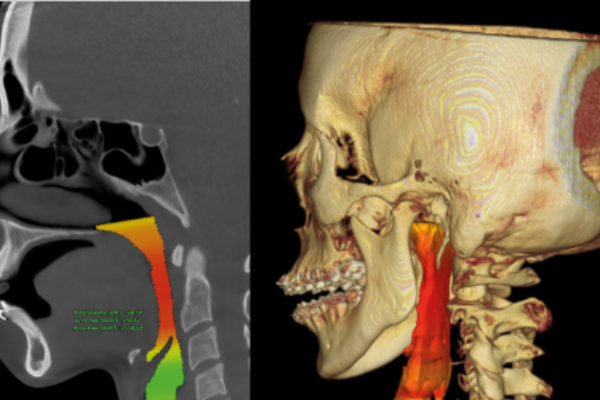

CBCT Cráneo Completo

Newton Giano

Sistema CBCT Newton Giano, líder en el sector de la radiología dental. Esta tecnología de  nos permite realizar diagnósticos detallados y precisos gracias a su capacidad para obtener imágenes tridimensionales de alta calidad del cráneo completo. Esto es fundamental no solo para la planificación y ejecución de tratamientos de implantología dental, sino también para la evaluación integral de la salud oral y general de nuestros pacientes.

Evaluación de la articulación y la mordida

Evaluar la articulación temporomandibular es esencial para garantizar la funcionalidad adecuada y evitar problemas.

Diagnóstico Vía aérea y otras patologías

El diagnóstico de la vía aérea y estructuras relacionadas es crucial para mejorar la calidad de vida.